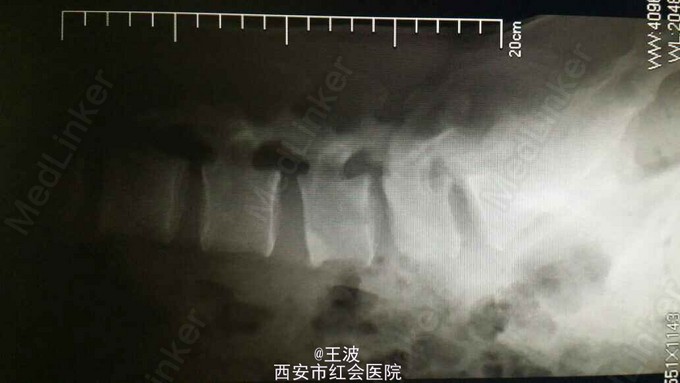

腰椎结核伴椎旁脓肿

脊柱生理弯曲存在,无畸形,腰4,5棘突及椎旁压痛明显,肢体抬高实验阴性,加强实验阴性,生理反射存在,病理反射未引出,辅助检查示:腰45椎体结核、椎旁脓肿形成。骶1、2椎管脓肿

初步诊断:腰4、5椎体结核并椎旁脓肿形成、骶1、2管囊肿 正规抗结核治疗,择期手术

鉴别诊断:脊柱肿瘤,多见于高龄患者,有原发灶,且改患者影像学不支持肿瘤